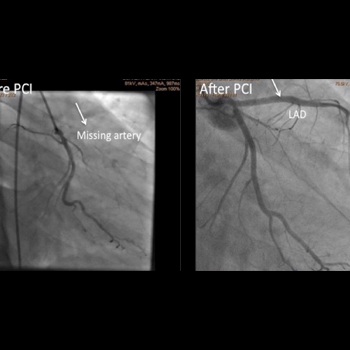

Chronic Total occlusion (CTO) angioplasty

Chronic Total occlusion…

Learn more